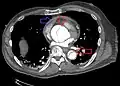

Computed tomography

Computed tomography angiography is a fast, non-invasive test that gives an accurate three-dimensional view of the aorta. These images are produced by taking rapid, thin-cut slices of the chest and abdomen, and combining them in the computer to create cross-sectional slices. To delineate the aorta to the accuracy necessary to make the proper diagnosis, an iodinated contrast material is injected into a peripheral vein. Contrast is injected and the scan performed using a bolus tracking method. This type of scan is timed to injection to capture the contrast as it enters the aorta. The scan then follows the contrast as it flows through the vessel. It has a sensitivity of 96 to 100% and a specificity of 96 to 100%. Disadvantages include the need for iodinated contrast material and the inability to diagnose the site of the intimal tear.

-

CT with contrast demonstrating aneurysmal dilation and a dissection of the ascending aorta (type A Stanford) -